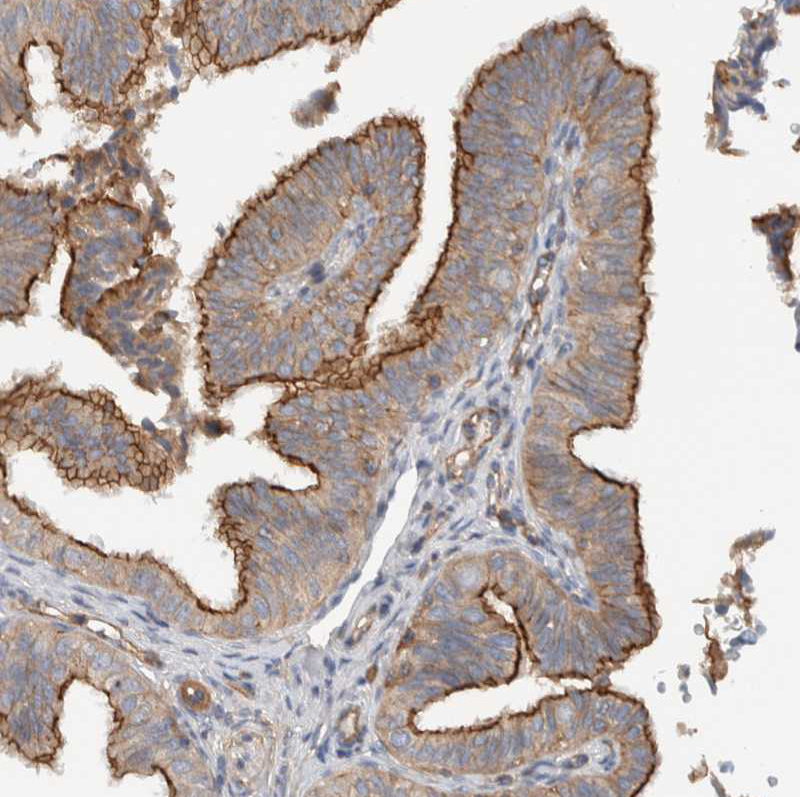

Immunohistochemical staining of human cerebral cortex, fallopian tube, liver and prostate using Anti-MPRIP antibody HPA022901 (A) shows similar protein distribution across tissues to independent antibody HPA022034 (B).